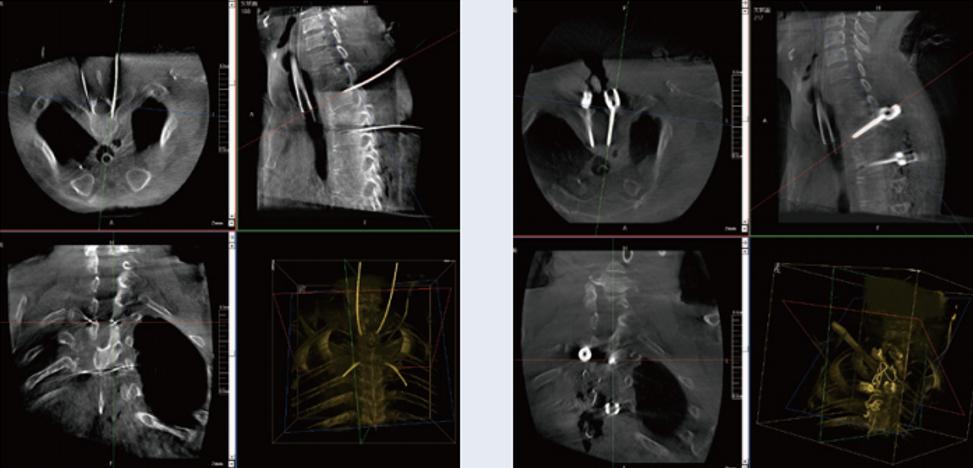

螺釘規(guī)劃后的圖像

植入螺釘后的圖像

術(shù)中三維C臂與骨科導航機器人配合應(yīng)用,實現(xiàn)準確定位,確保了手術(shù)安全、快捷完成。術(shù)后二維、三維影像顯示手術(shù)效果良好,達到預期目的。

普愛醫(yī)療三維C臂提供了高質(zhì)量的術(shù)中實時三維圖像數(shù)據(jù),保障了骨科導航機器人手術(shù)的準確度和安全性,取得不錯的手術(shù)效果。同時,三維C臂特有的斷層成像,能幫助醫(yī)生在術(shù)中非常直觀地判斷螺釘植入的準確度。